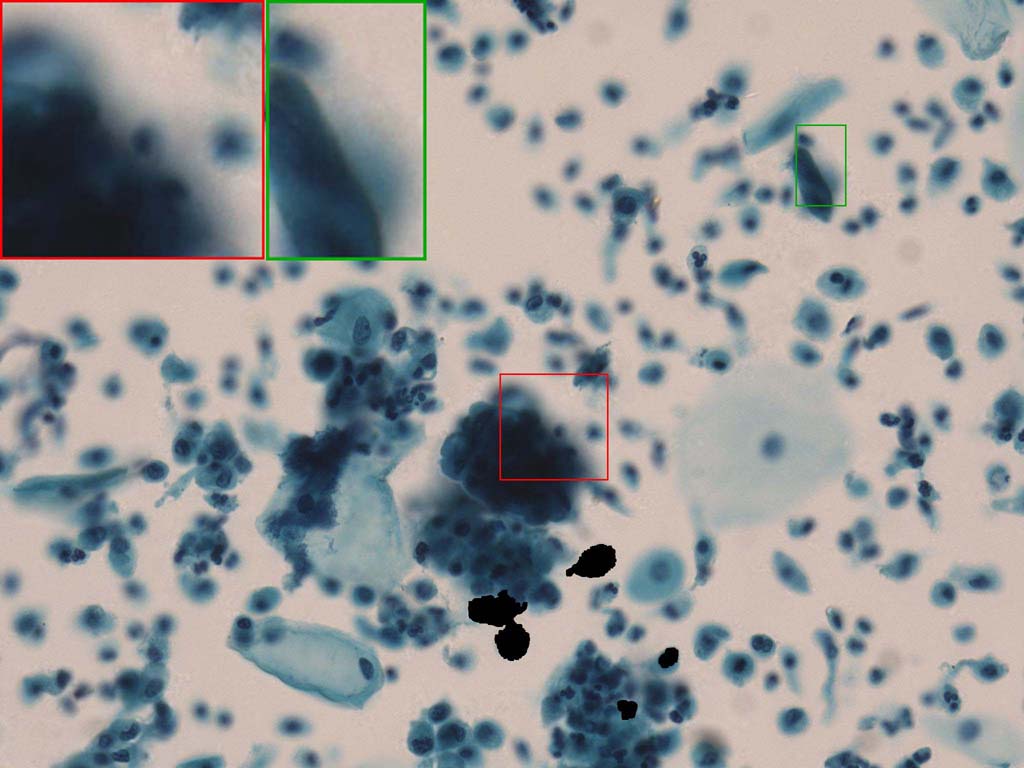

To demonstrate the effectiveness and efficiency of the proposed image fusion method , we conduct a set of comparative experiments on three image datasets. The first is composed by 8 pairs of multi-modal medical images and the second one contains 15 pairs of multi-focus gray or color natural images. These two datasets are often used in many related papers and some examples are shown in Figure 3(a) and Figure 3(b). The third one is a new multi-focus cervical cell image dataset collected by ourselves, which consists of 15 groups of color images and each group contains a series of multi-focus cervix cell images with size of or , etc. Some source examples are shown in Figure 3(c). Our source code implemented in C++ along with the new multi-focus cervical cell image dataset is available online.

Figure 9, Figure 10 and Figure 11 show the comparative fused results of the multi-focus cell images shown in Figure 3(c). For clarity, we also present a closeup view in the right-bottom of each sub-picture in Figure 9 and Figure 10. As shown in the close-up views of Figure 9, the fused images based on DSIFT, IM, MWGF and BF methods are extremely blurred in the boundary and fail to keep the details of cell nucleus. Furthermore, the DTCWT and NSCT based methods produce halo artifacts in the fused images, while GFF and CNN based methods fail to preserve the small cell nucleus. LP-SR based method nearly works fine which keeps the most of the details of the small size cells, but the integrity of the clustered large size cells is damaged. Fortunately, in our proposed method, the integrity of the clustered large size cells is preserved and most of the isolated small size cells are maintained from the original images, which demonstrates the best visual quality.

Similarly, as shown in the close-up views of Figure 10, the fused images from DSIFT, IM, MWGF and BF are blurred and lose some nucleus details, while the results from DTCWT, GFF, CNN and NSCT produce halo artifacts. LP-SR based method can keep details well but also produces halo artifacts and other noise. Our method can preserve the focused areas of different source images well without introducing any artifacts. For the example illustrated in Figure 11, the fused images generated by DSIFT, DTCWT, IM and NSCT all fail to preserve the focused areas of different source images and result in extremely blurred images. The GFF, CNN, MWGF and BF based method introduces a lot of color distortion of the nucleus regions and the obvious halo artifact. The result of LP-SR based method is close to the one of our method but introduces some odd color distortion. Again, our method produces fused image which can preserve the focused areas of different source images well without introducing any artifacts.